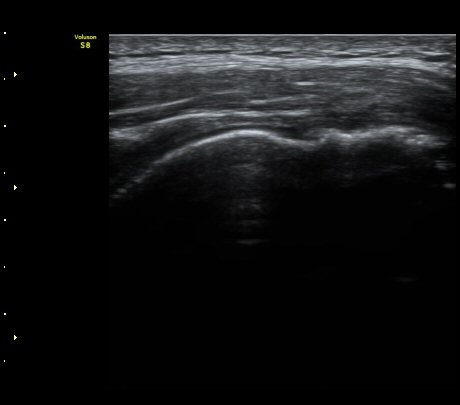

±ØÇ졂 Á¾´Ü¸é°Ë»ç¿¡¼­ ±ØÇϰÇÀº ºñ±³Àû Á¤»ó ¼Ò°ßÀ» À¯ÁöÇÔ(»çÁø 3).